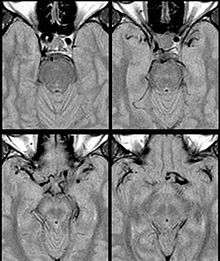

Internal Carotid Artery dolichoectasia is particularly interesting because the artery normally already contains one hairpin turn. Seen in an MRI as two individual arteries at this hairpin, a carotid artery dolichoectasia can progress so far as to produce a second hairpin turn and appear as three individual arteries on an MRI. In the case of a dolichoectasia of the Internal Carotid Artery (ICD), the pathogenesis is primarily related to compression of the Optic Nerves at the Optic Chiasma (see Fig. 1 and 2).